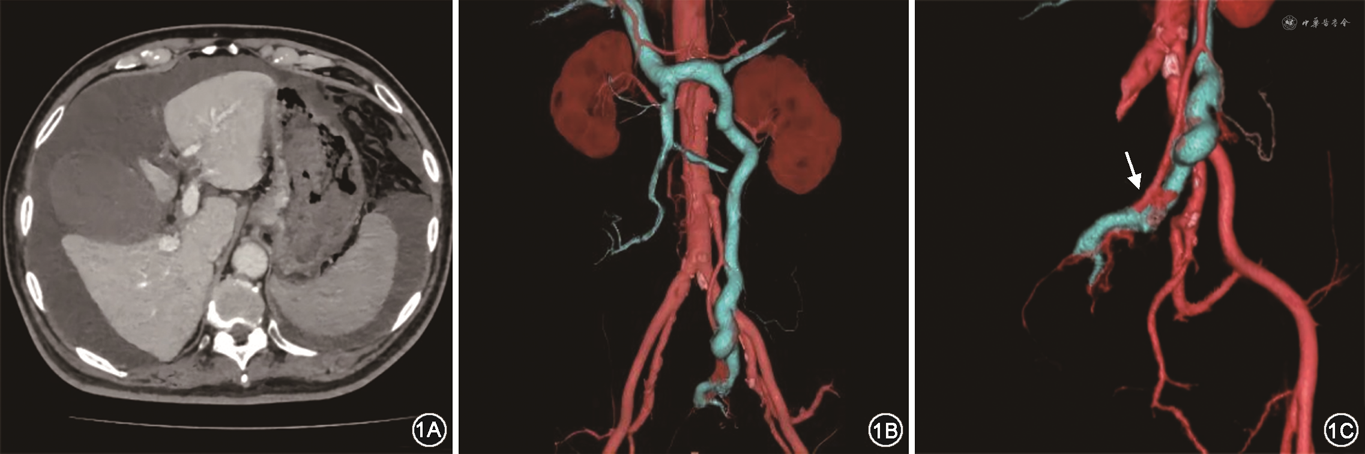

2021年11月3日,患者全腹增强CT及腹部血管三维重建结果示大量腹水,门静脉主干及脾静脉增宽、食管胃底静脉迂曲增粗,动脉期门静脉、脾静脉及肠系膜下静脉提前显影,肠系膜下静脉明显增宽,肠系膜下动脉远端的直肠上动脉与肠系膜下静脉在骶前相互沟通,形成紊乱血管网,提示直肠上动脉与肠系膜下静脉之间存在动静脉瘘(图1),余未见明显异常。患者于2021年11月4日20:20相继排5次暗红色便,血压降至72/47 mmHg(1 mmHg=0.133 kPa),行急诊胃镜检查见距门齿约30 cm以下食管至贲门4条曲张静脉,形态呈结节状,最粗直径约0.6 cm,曲张静脉间可见血管网,红色征阳性;胃内少许咖啡色液,胃底可见团块样曲张静脉,表面可见血栓,给予组织胶4.5 ml分4点注射;十二指肠球部及降段可见少许暗红色血液,冲洗后可见十二指肠乳头对侧黏膜略凹陷、有活动性渗血,给予止血夹2枚。观察再未有活动性出血。术后患者生命体征平稳,未再出现消化道出血。